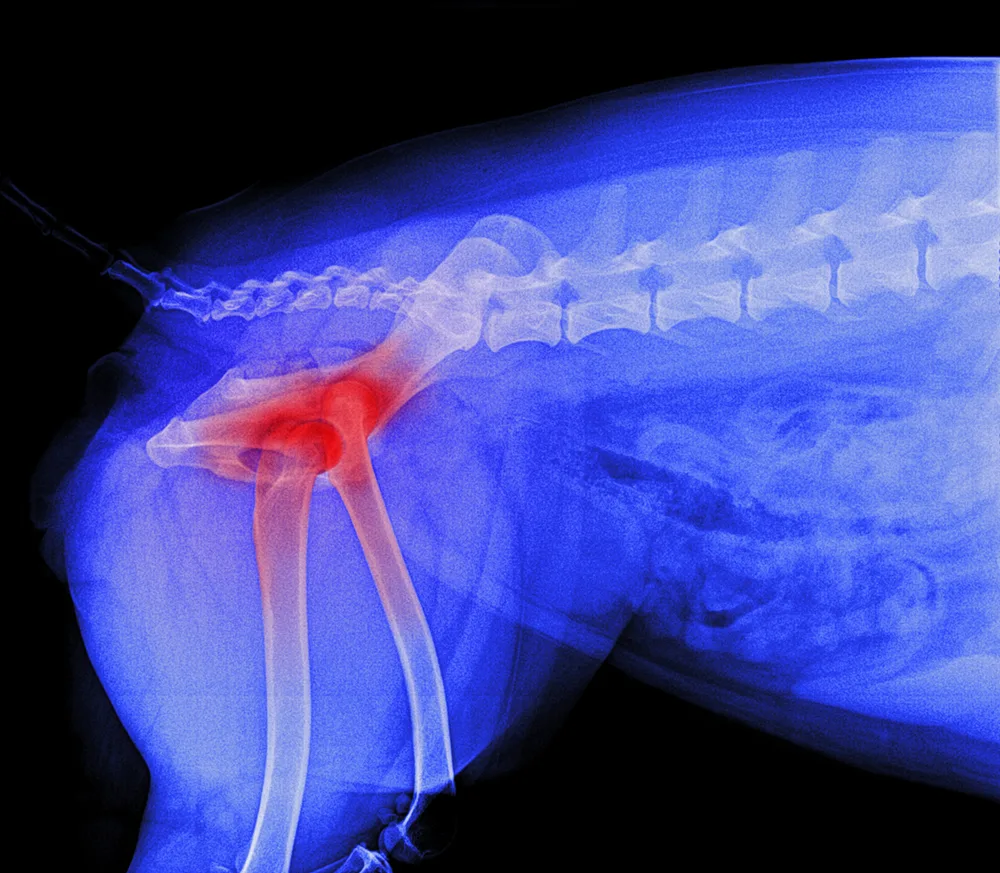

Osteoarthritis (OA) is one of the most common chronic conditions in dogs, and one of the most misunderstood. Many owners attribute stiffness, slowing down or irritability to ‘just getting old,’ when in reality these are signs of pain. Until recently, canine OA treatment options focused mainly on non-steroidal anti-inflammatory drugs (NSAIDs), joint supplements, weight management and physiotherapy.

But the release of Librella® (bedinvetmab) has introduced an entirely new class of pain relief: one that is long-acting, targeted, and specifically designed for chronic arthritis in dogs. If your dog has OA or is showing early signs, this medication may be part of the future of comfort-focused care.

Stiffness after rest, especially when rising from sleep, is one of the earliest and most common signs of canine osteoarthritis, particularly in middle-aged and senior dogs.

SIGNS SUGGESTING ARTHRITIS

• Slow to stand after lying down

• Hesitation on stairs or jumping into cars

• ‘Bunny hopping’ or altered gait

• Less interest in long walks

• Stiffness that improves as they ‘warm up’

• Irritability when touched over hips, back or elbows

• Lyme disease or immune-mediated joint disease

A vet exam and possibly X-rays are the best way to confirm.